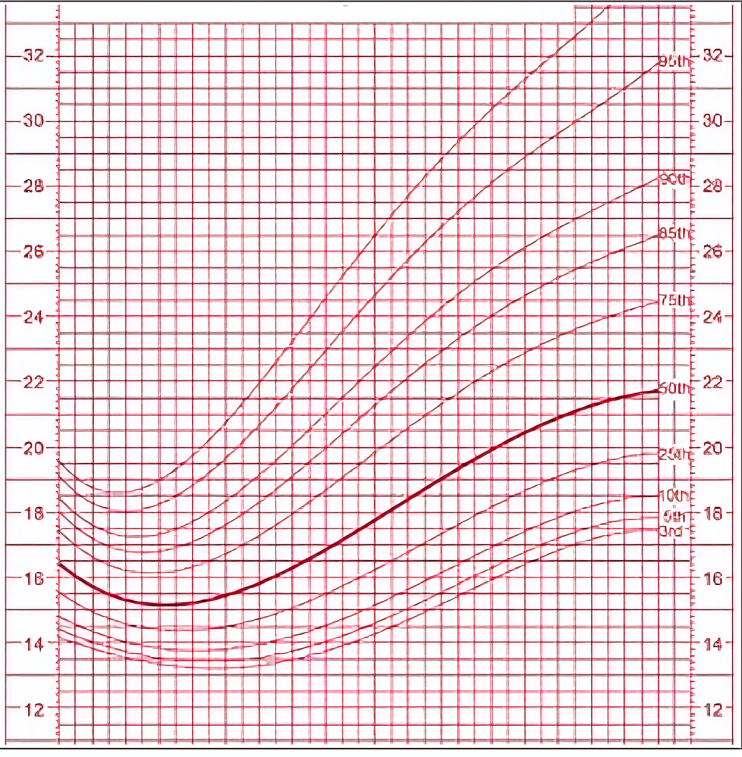

Le retard de croissance intra-utérin (RCIU) est un terme générique qui regroupe les ralentissements et “cassures” de la courbe de croissance intra-utérine.

On oppose classiquement deux types de RCIU :

- Le type I ou harmonieux ou symétrique (30 % des cas) : Le périmètre crânien, le périmètre abdominal, la taille et le poids sont simultanément altérés (< 10ème percentile). Il est d’apparition précoce au 2ème trimestre de la grossesse ; le retard de croissance apparaît d’emblée dès le début de la période fœtale. Les trois paramètres de la croissance sont altérés dans les mêmes proportions avec, en corollaire, microcéphalie et petite taille.

- Le type II ou dysharmonieux ou asymétrique (70 % des cas) : Le périmètre crânien est normal tandis que le périmètre abdominal, le poids et parfois la taille sont diminués (< 10ème percentile). La croissance cérébrale est relativement conservée ; en effet, grâce à un phénomène de redistribution vasculaire, le pôle céphalique est préservé longtemps. Il est d’apparition tardive au 3ème trimestre de la grossesse. La cause en est la malnutrition due à des lésions placentaires altérant les échanges fœto-maternels.